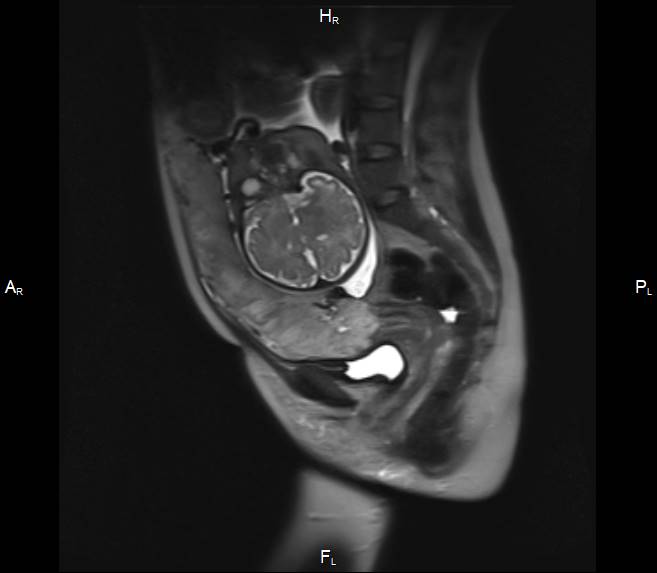

Госзадание «Инновационный метод комплексной диагностики патологии плацентации для прогнозирования течения беременности с использованием технологии ультразвукового и магнитно-резонансного сканирования с диэлектрической подкладкой на основе метаматериалов».

Результаты: Была разработана методика мультипараметрического МРТ исследований плаценты с использованием диэлектрической подкладки на основе метаматериалов, улучшающей локальную однородность магнитного поля и повышающей соотношение сигнал/шум у пациенток с патологией прикрепления плаценты.

Первичный, или «материнский» этап, длительностью 3–5 минут, при котором получаемые Т2-ВИ многоплоскостные ортогональные МР-изображения (рисунок 1) ориентируются согласно анатомии беременной; целью его является оценка сегментарного расположения плацентарного диска в полости матки, контуров и размеров матки.

| Рисунок 1 – Беременность 36 нед. МРТ плаценты. Первичный, «материнский» этап исследования. Т2 ВИ в сагиттальной (а), корональной (б) и аксиальной (в) плоскостях | ||

Завершающий, или «тазовый» этап, длительностью не более 5–10 мин, при котором прицельно оценивается нижние сегменты матки, внутренний зев, шейка матки, мочевой пузырь, смежные ткани и органы таза беременной с целью выявления критериев прорастания плаценты, которые могут соответствовать 3 (a, b, c) степени согласно классификации FIGO (2018) для клинической диагностики группы плацентарных нарушений адгезивно-инвазивного спектра (рисунок 2).

| Рисунок 2 – Беременность 36 нед. МРТ плаценты. Основной, «плацентарный» этап исследования. Варианты позиционирования срезов для получения ортогональных изображений плаценты в косо-сагиттальной (б), косо-корональной (в) и косо-аксиальной (г) плоскостях относительно анатомии беременной по МР-изображениям первичного этапа (а) | ||